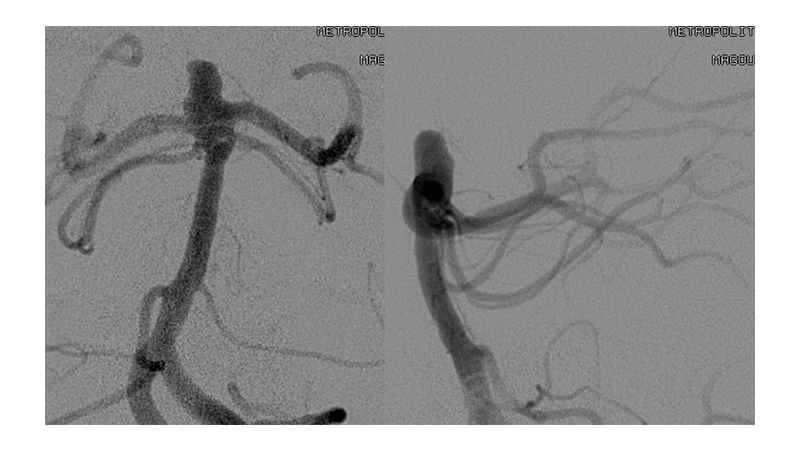

Εικόνα 1: Μη ραγέν ανεύρυσμα της κορυφής της βασικής αρτηρίας, το οποίο έχει ευρύ αυχένα.

Στην διαμόρφωση του αυχένα συμμετέχουν τα Ρ1 τμήματα των οπισθίων εγκεφαλικών αρτηριών αμφοτερόπλευρα.